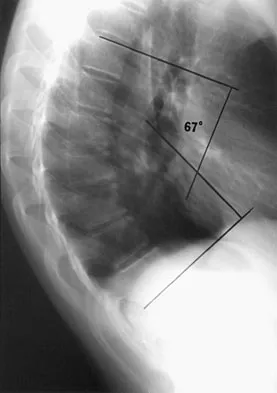

Figure 16 shows the lateral radiograph of a patient who is scheduled to undergo an anterior cruciate ligament (ACL) reconstruction. If the graft is tensioned at 20 degrees of flexion and the femoral tunnel is created by passing a reamer over the guide wire marked "A," the resulting ligament reconstruction will excessively